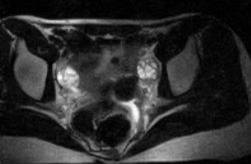

Здоровье женщин: МРТ при цистаденофиброме яичника